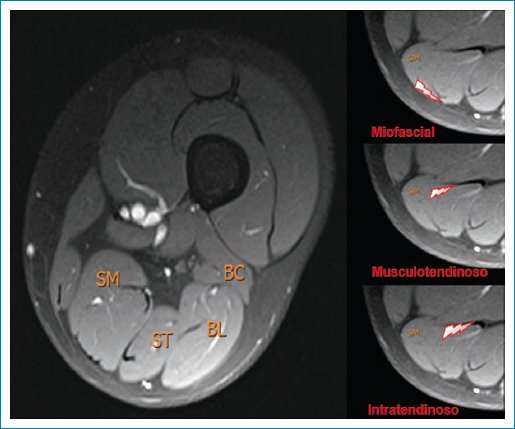

Los grados 0-3 son lesiones de espesor parcial. Luego, la lesión se subclasifica según el sitio anatómico de la lesión (Fig. 2):

• −Tipo a: miofascial.

• −Tipo b: musculotendinosa.

• −Tipo c: intratendinosa.

Figura 2. RM de muslo derecho: axial FS. Ilustración de isquiotibiales y sitio anatómico de lesión muscular. SM: semimembranoso; ST: semitendinoso; BL: bíceps femoral cabeza larga; BC: bíceps femoral cabeza corta.